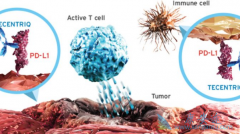

PD-L1 抑制剂atezolizumab在首次获批上市时通过的适应症为膀胱癌,那atezolizumab能否作为膀胱癌患者的一线用药呢?一项II期临床试验IMvigor210对此做出了评估。研究纳入了两组患者,第一组招募了119名不适合顺铂化疗的晚期初治患者,使用PD-L1抗体Tece ...

Tecentriq是FDA批准的第一个 PD-L1 抑制剂,上市获批的适应症为膀胱癌。Tecentriq的安全性和有效性透过一项纳入310例局部晚期或转移性尿路上皮癌的单臂临床研究进行了评价。总体上,肿瘤出现全部或部分缩小的患者比例(客观应答率)为14.8%,该作用可持 ...